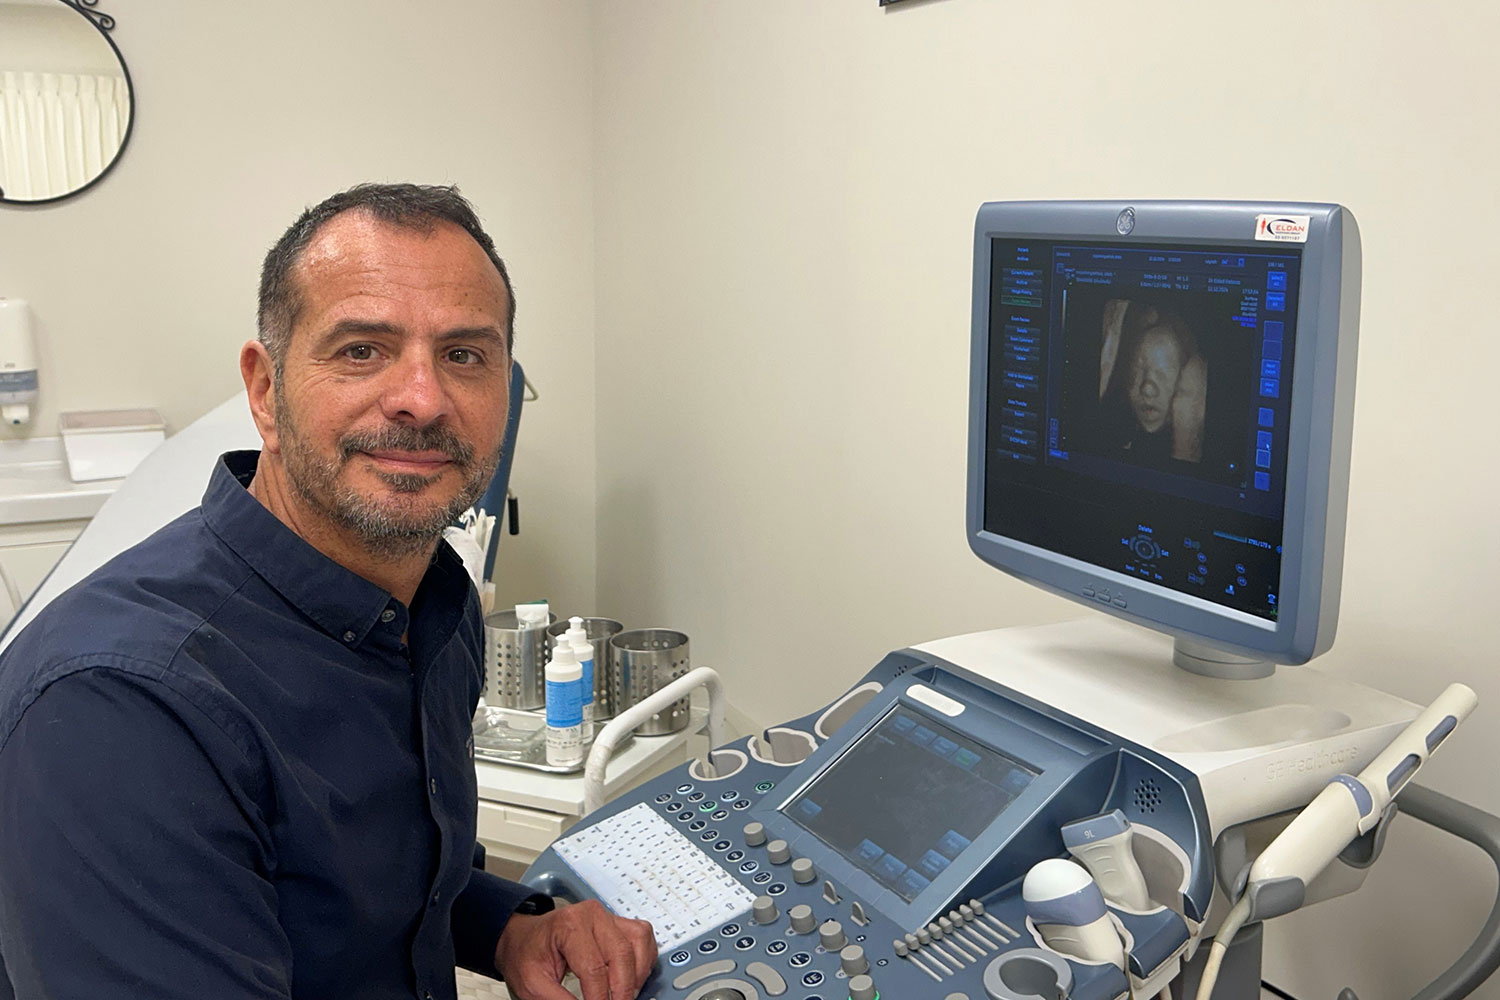

פרופסור אלדד קטורזה מפענח בדיקות MRI עוברי ונותן ייעוץ וחוות דעת שניה בתחום.